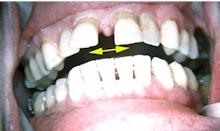

Il ne suffit pas d'observer les arcades en occlusion pour affirmer qu'il n'existe aucune pathologie comme cela a pu être déclaré par un expert judiciaire.

La récidive de la perte d'une restauration d'angle incisif doit éveiller l'attention du praticien sur la possibilité de problèmes occlusodontiques.

Il en va de même pour une fêlure qui aboutira à la fracture.